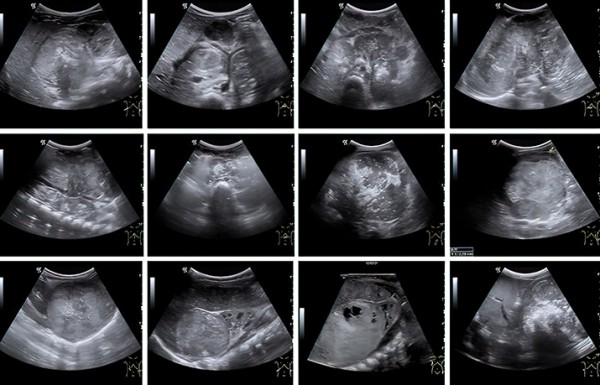

К сожалению, у значительной части пациентов на момент постановки диагноза болезнь уже в распространенной форме. Чаще всего опухоль распространяется в лимфатические узлы, печень, кости и костный мозг (см. рис. 1).

Хотя окончательный диагноз нейробластомы выносится на основе биопсии, взятой во время операции, впервые эту опухоль обнаруживает врач УЗД при скрининговом исследовании плода, на профилактическом осмотре или при обследовании ребенка, которого привели с конкретными жалобами.

Во время УЗИ на амбулаторном этапе забрюшинная опухоль, как правило, определяется по достижении так называемого диагностического объема в несколько кубических сантиметров. При этом врач уверенно может установить факт наличия образования, его эхоструктуру, чего уже достаточно для направления ребенка на дообследование (см. рис 2).

Рисунок 2. Сонографические варианты нейробластомы.

Наибольшие трудности специалист УЗД испытывает при установлении органной принадлежности опухоли, когда она уже достигла больших размеров. К примеру, медиана диагностического объема впервые установленной нейробластомы у младенца составляет 75 (26–208) см3, а для опухоли почки и того больше — 317 (226–524) см3. Именно эти новообразования приходится дифференцировать, в том числе и в онкологическом центре, т. к. химиотерапевтическое лечение опухоли Вильмса в ряде случаев начинают по результатам диагностики на основе визуализирующих методов исследования.